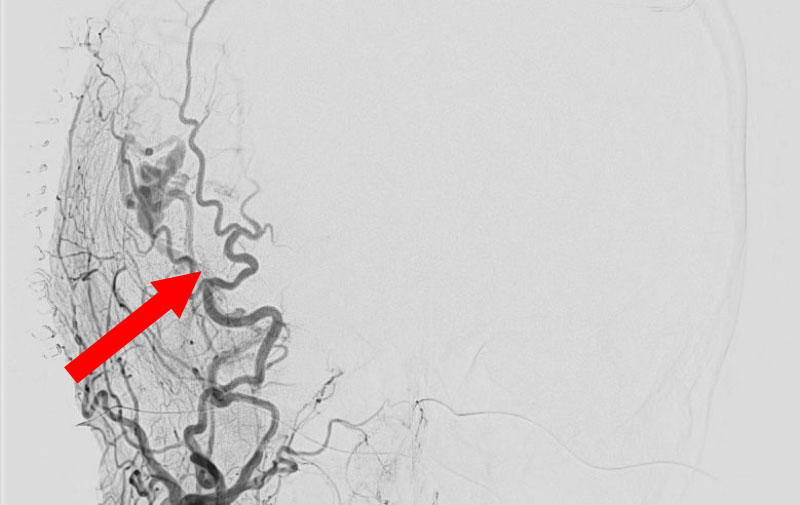

'25年10月

硬膜動静脈瘻

50代

救急外来

No.1591 手術前

No.1591 手術中

No.1591 手術後